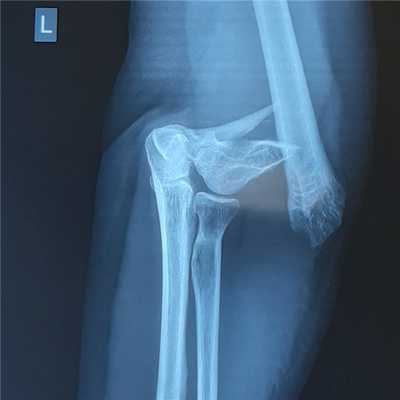

На представленных ниже рентгенограммах локтевого сустава определяется оскольчатый перелом мыщелков левого плеча с 4 большими фрагментами.